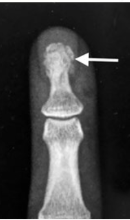

What type of fracture is this?

Tuft/Burst

What is a tuft/burst fracture?

Caused by crushing blow to distal finger or thumb (slamming in a door/hammer)